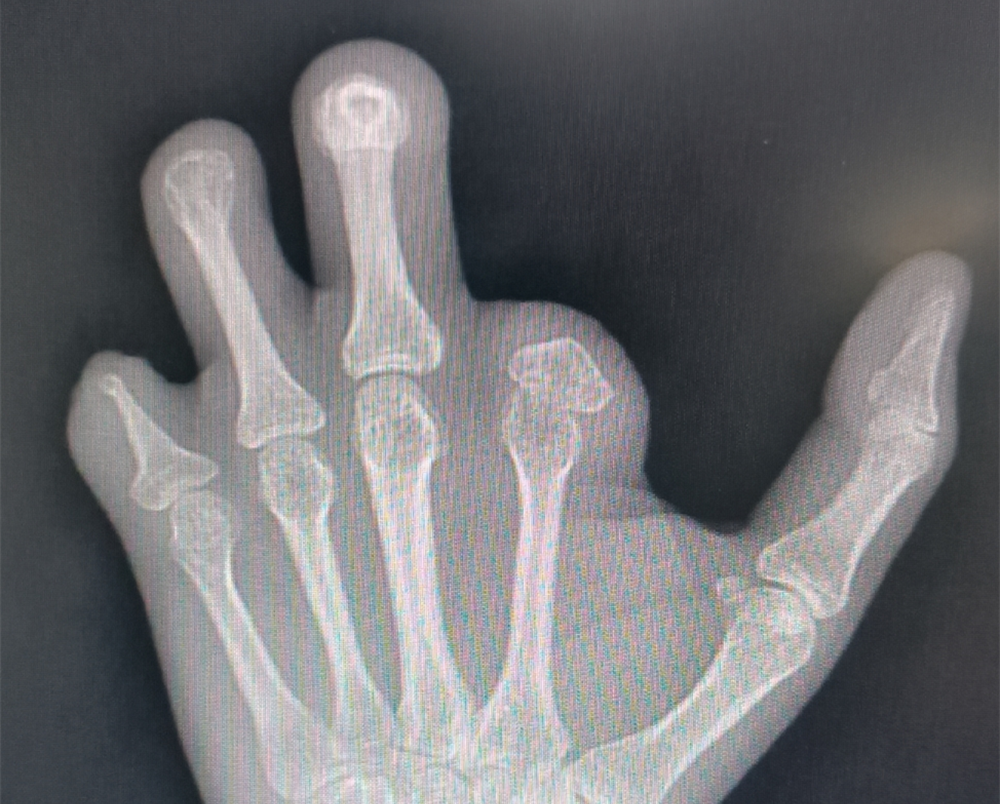

您的位置: 首页>科室导航>骨科>修复重建显微外科>科室新闻